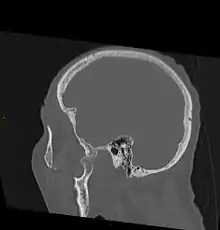

As with other joint dislocations, clinical history and examination are important for diagnosis. Commonly, plain and panoramic X-rays are used to determine the relative position of the mandibular condyle. If a complex or unusual injury is suspected, computed tomography is most reliable in diagnosing dislocation and possibly associated fractures or soft tissue injuries.

CT image demonstrating jaw dislocation